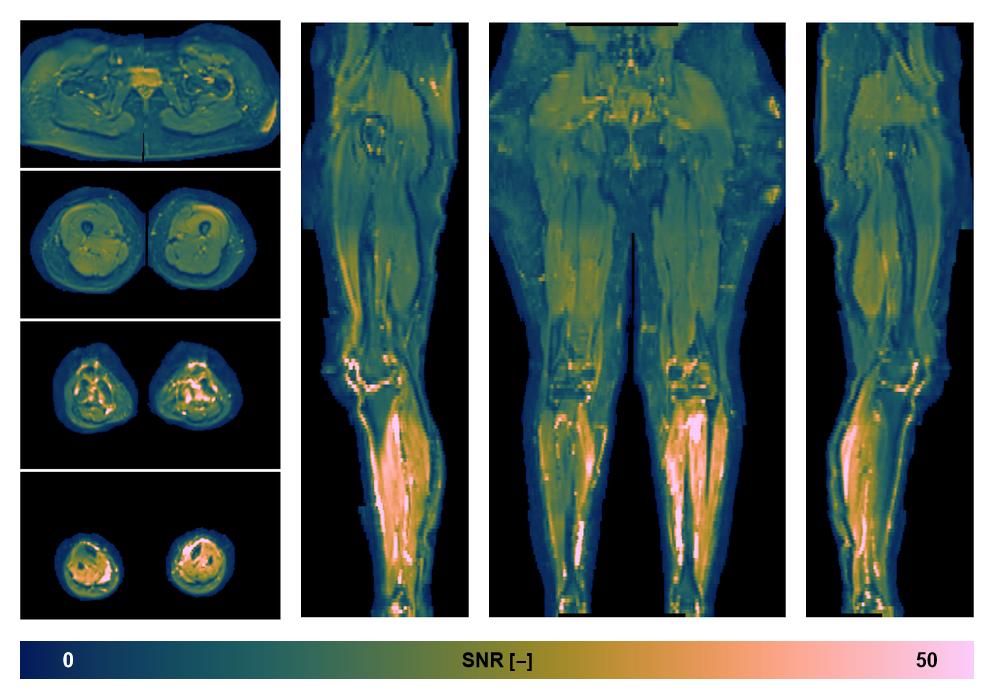

• SNR of the unweighted image

SNR distribution of the unweighted diffusion data.